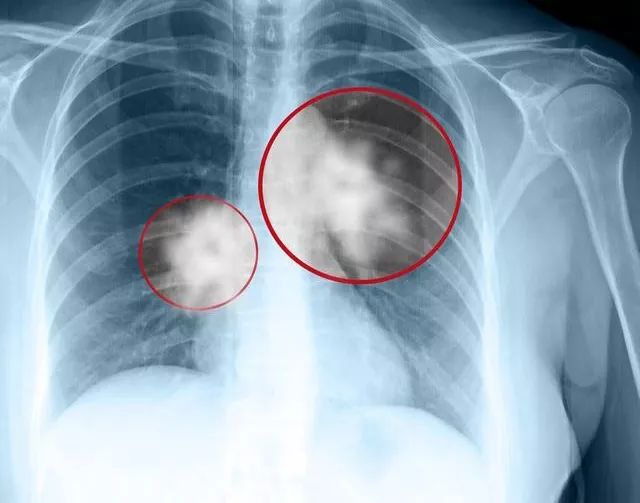

以痰中带血为首发症状的肺癌约占所有肺癌的20%,肺癌出现痰中带血一般系中央型肺癌居多,周围型肺癌很少出现痰中带血。这是因为中央型肺癌一般临近肺门,当肿瘤侵犯小血管或者毛细血管时会出现少量出血,并从支气管排出,表现为痰中带血。肿瘤浸润血管壁是个缓慢的过程,所以肺癌咯血的特征为间断性或持续性、反复少量的痰中带血丝,或少量咯血。另外肿瘤组织血供丰富,且都是畸形血管,剧烈咳嗽时会引起肿瘤内小血管破裂而致出血。

所以吐血丝并不是判断肺癌严重程度的指标,很多早期中央型肺癌也会出现痰中带血,而极晚期的周围型肺癌并不会出现痰中带血。还有一些小细胞肺癌肺部病灶很小的时候就出现骨转移、脑转移,这才是非常严重的。不过这个提问者已经说了肺癌后期,那说明分期很晚,病情已经很严重了,治疗上可能只能选择止血等对症治疗。如果肿瘤组织巨大,且出现癌性空洞时,或者肿瘤侵犯大血管,也可能出现大量咯血,大咯血有可能引起患者出现窒息,引起呼吸衰竭和休克,甚至死亡。